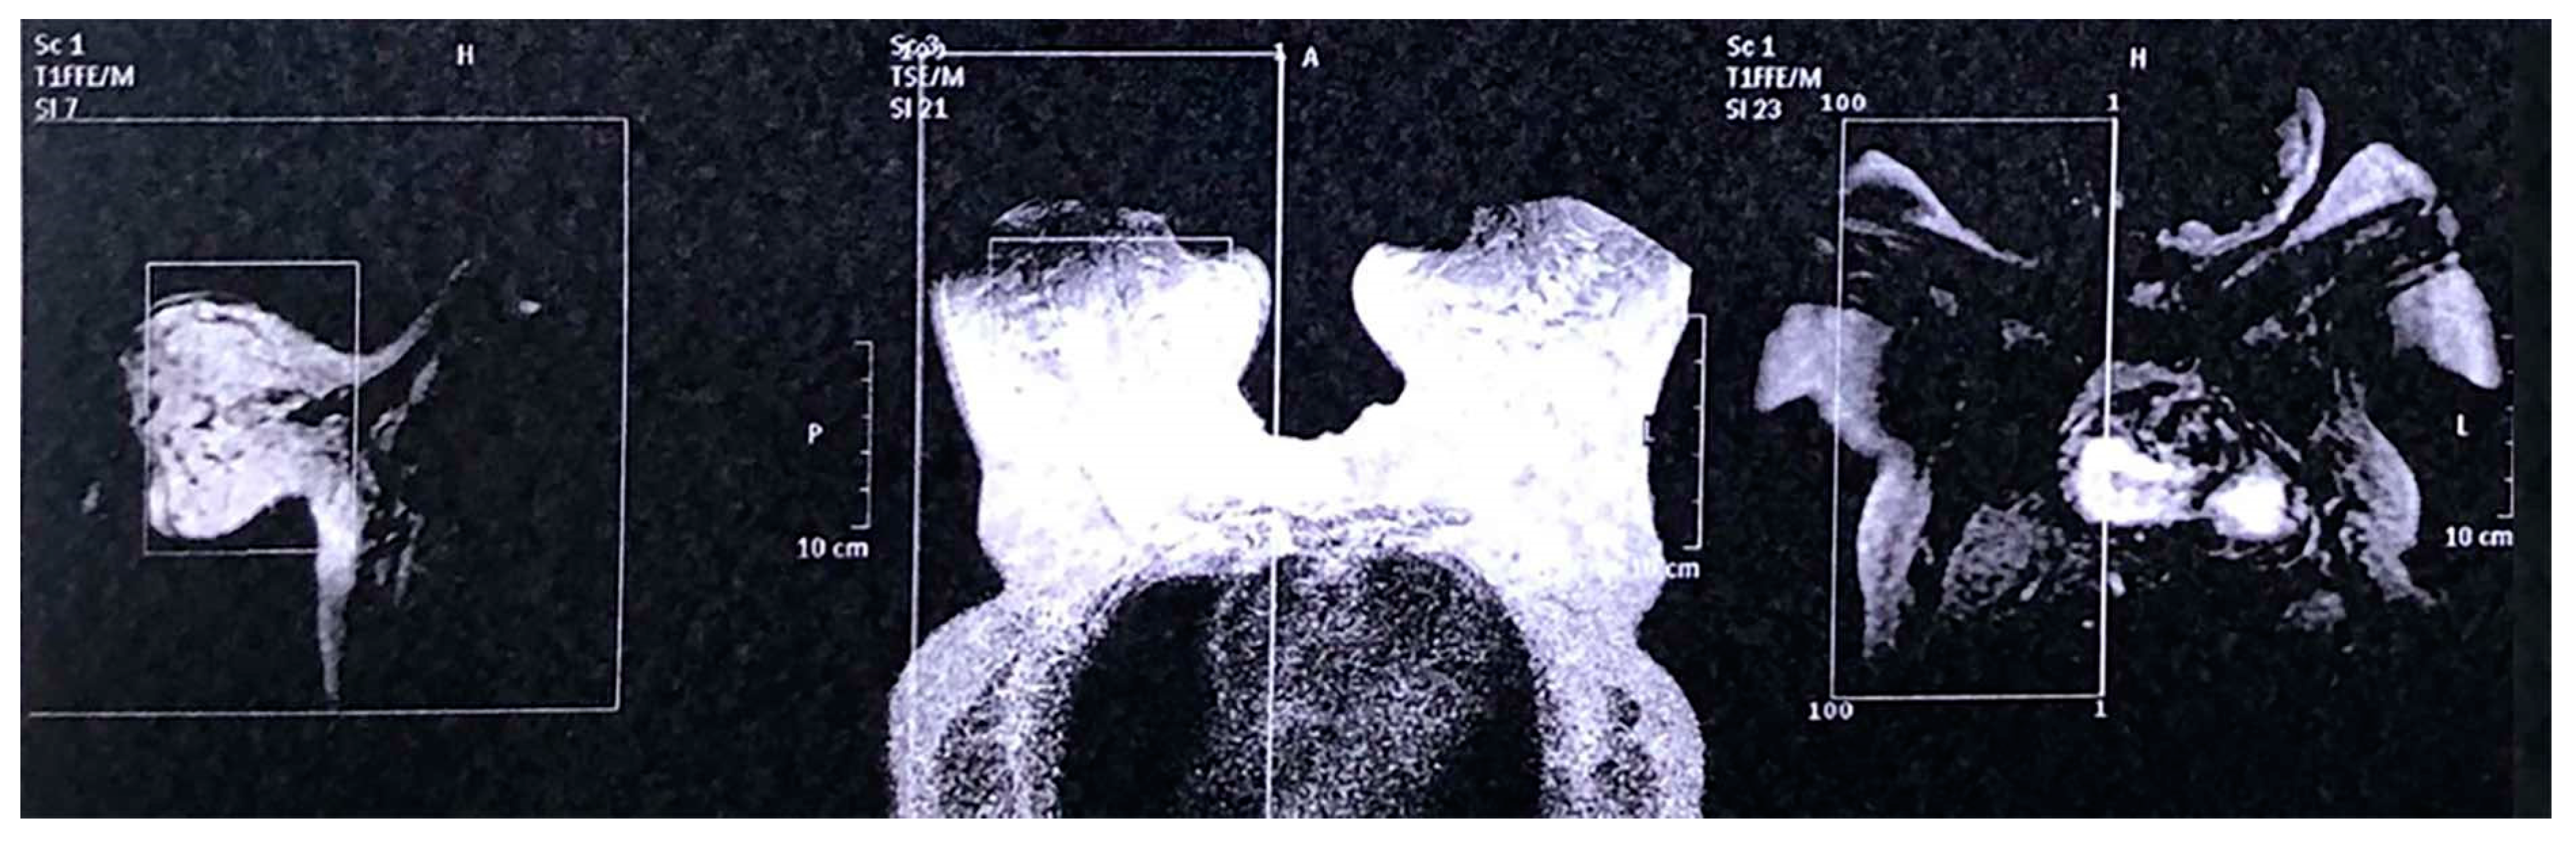

Breast ultrasound (Figure 2), Mammography (Figure 3A–C) and Magnetic Resonance Imaging (Figure 4) were non-conclusive (BI-RADS 0). Considering the rare case of a bilateral malignancy and the peau d’ orange appearance, core biopsy was deemed necessary for both breasts, including both actual breast tissue and skin. The day of core biopsy, clinically palpable lymph nodes were significantly shrunken in the left axilla and were not palpable in the right axilla and no further investigation of the axilla region was deemed necessary.

Figure 2.

Ultrasound of both breasts without conclusive findings.

Figure 4.

Magnetic Resonance Imaging of both breasts without conclusive findings.